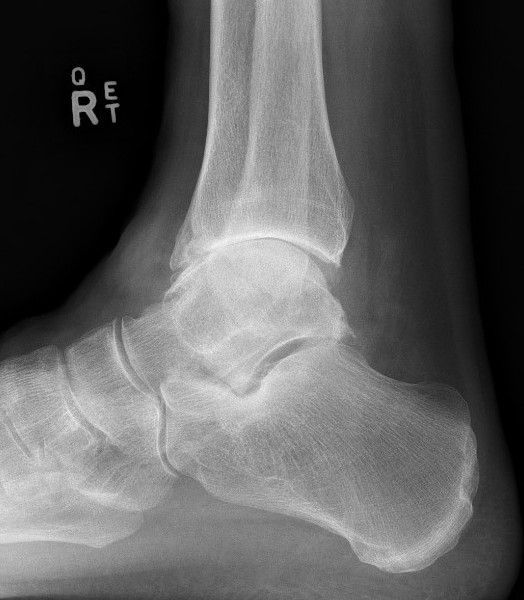

- position foot, check with image intensifier

- two cannulated screws from medial tibia to talus dome / neck

- +/- screw medial malleolus to talus

- +/- screw fixation fibular / onlay graft